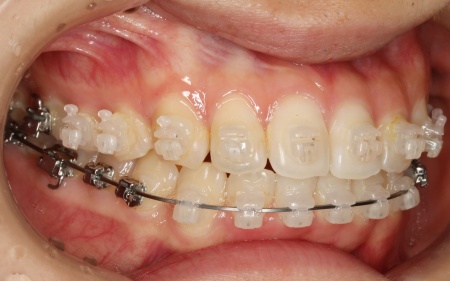

治療中